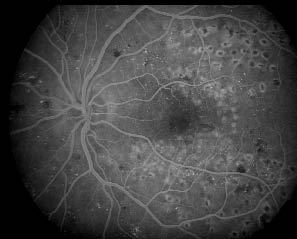

Mynd 2. A: Æðamyndataka með fluorescein efni af sjúklingi með makúlubjúg vegna sykursýki. Slagæðlingar og bláæðlingar eru fylltir með fluorescein litarefninu, en litarefnið er ekki farið að leka út í vefinn enn þá. Mikið er af örum eftir leysimeðferð.

Mynd 2. B: Síðan má sjá að þegar litarefnið fer að leka út úr æðunum nálægt makúlu myndast miðlægt gráleitt ský.